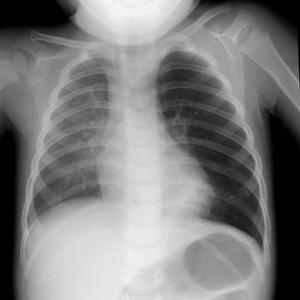

Определить наличие воздуха в плевральной полости самостоятельно невозможно. Начало этого процесса можно заподозрить только по клиническим проявлениям заболевания. Обратите внимание на изображение пневмоторакса:

Диагностика пневмоторакса осуществляется с помощью рентгенографии. На рентгеновском снимке он будет представлен как светлый участок, не имеющий легочного рисунка. Это состояние возникает в результате накопления воздуха в плевральной полости.

При длительном течении заболевания наблюдается спадание легочной ткани, что отчетливо видно на рентгеновском снимке.

Для подтверждения диагноза пневмоторакса используются различные методы визуализации. Наиболее распространенным является рентгенография грудной клетки, которая позволяет выявить наличие воздуха в плевральной полости. На рентгеновских снимках пневмоторакс проявляется в виде темного пространства между легким и грудной стенкой, где отсутствует легочная ткань.